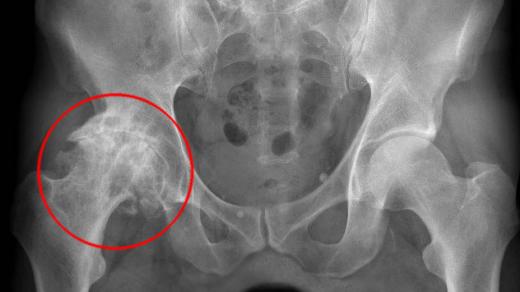

Bolest kyčle | Shutterstock

Kyčelní kloub je jedním z největších a nejzatěžovanějších kloubů v lidském těle. Když začne bolet, tělo si říká o pozornost – a čím dřív ji dostane, tím lépe.